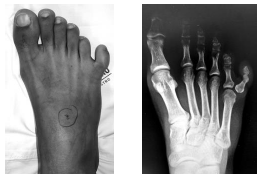

Segundo VENN-WATSON, a polidactilia ilustrada na Figura abaixo é classificada como do tipo

Fonte: arquivo da Banca examinadora